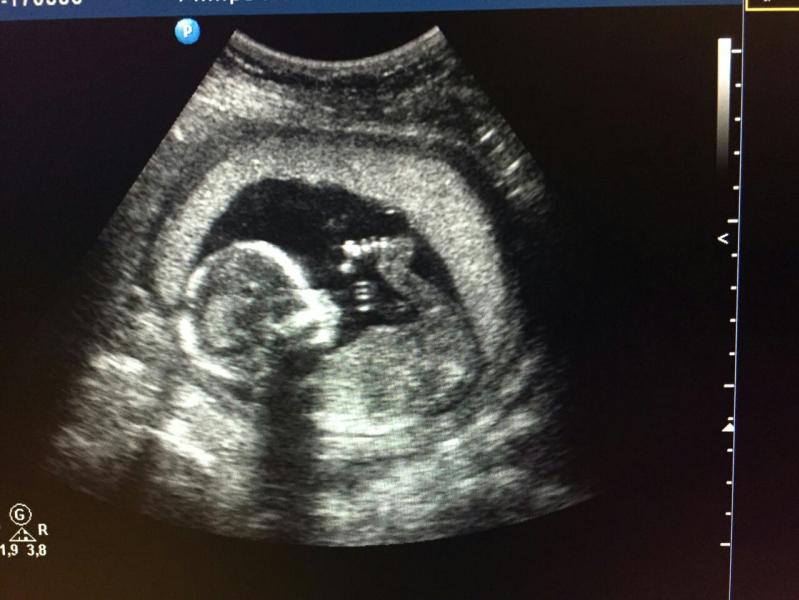

Ура,пацан!😀я прям с детства мечтала иметь 2 сына👬конечно хотелось разнополых деток,ну как бы попробовать а как это)))ну я довольна!Калугина чудо узист!забежала на 15 секунд- положительных эмоций огромный заряд😊еще и сфотать предложила пупса😻

Она сама предложила)у меня и телефон сел!иди говорит у мужа врзьми,я подожду))